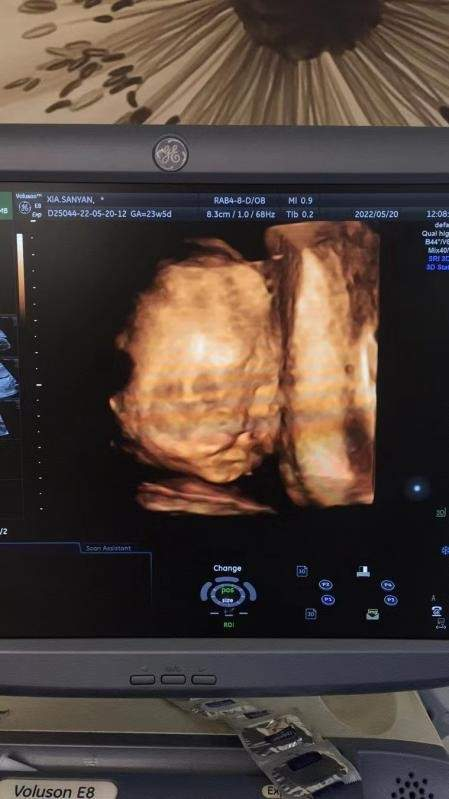

胎兒四維彩超影像

5月20日上午,懷孕23周的張女士來到武漢仁愛醫(yī)院準(zhǔn)備做四維彩超篩查。意外不期而至,武漢仁愛醫(yī)院超聲影像科主任王娟在檢查時對胎兒每個部位都進(jìn)行了仔細(xì)檢查,發(fā)現(xiàn)張女士腹中的寶寶患有先天性唇腭裂。

胎兒面部唇腭裂

當(dāng)?shù)弥@個結(jié)果后,張女士后悔不已,如今寶寶已經(jīng)23周,或?qū)⒚媾R出生后做唇腭裂手術(shù)。王娟安慰了她,并為她做了情況說明,張女士才慢慢將情緒穩(wěn)定下來。